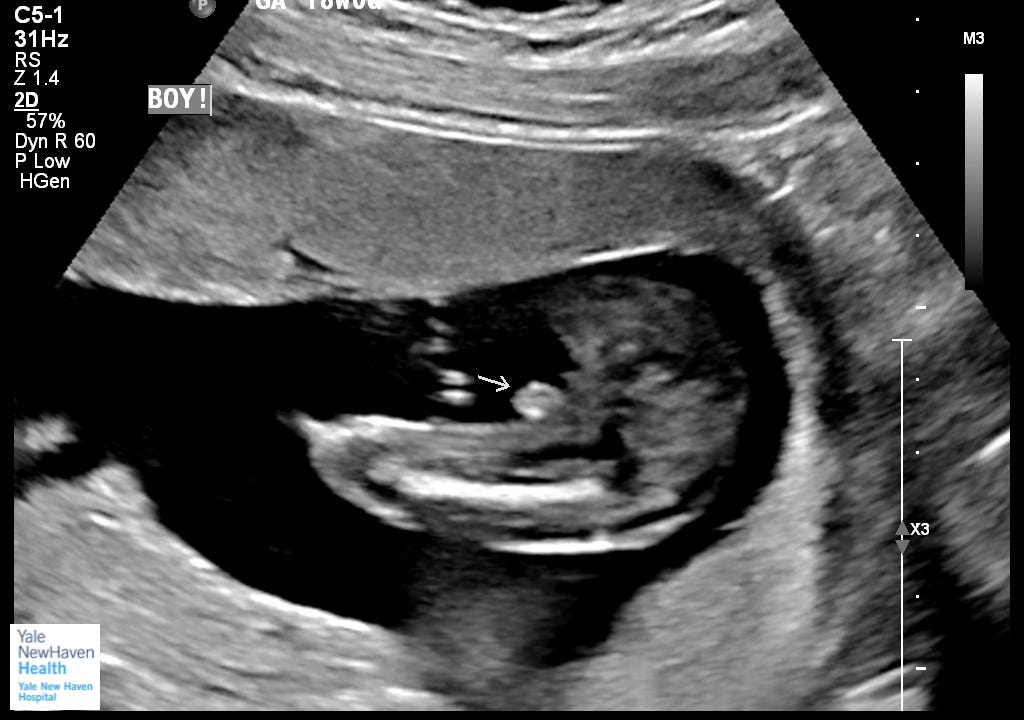

Are you having a boy or a girl?

We are having a boy! In April, God willing.